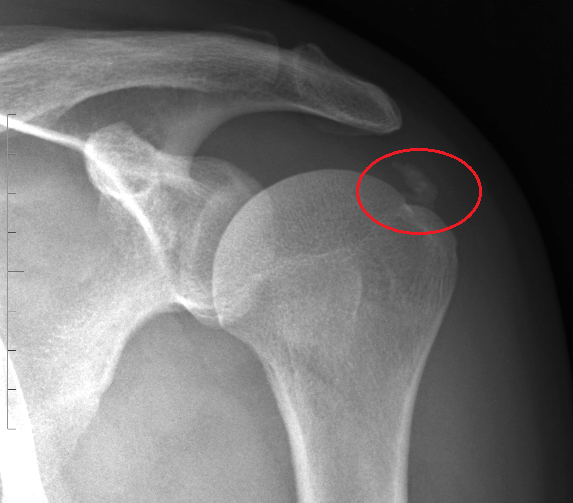

What can be seen on this X-ray?

Acute calcific tendonitis

What would the patient experiance in acute calcific tendoitis?

Acute onset of severe shoulder pain

What tendon is usually affected in acute calcific tendonitis?

Suprapspinatous tendon

What is the prognosis of acute calcific tendonitis?

Self limiting with pain easing as the calcification reabsorbs